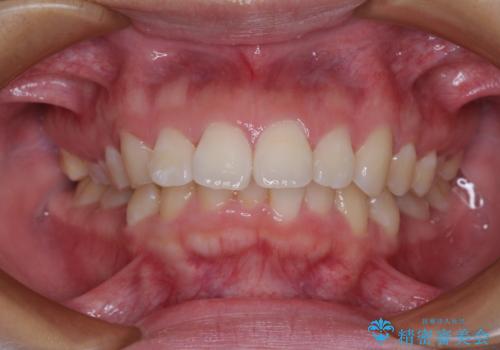

- 上顎前歯が飛び出していて唇がうまく閉じられないとのことで来院された患者様です。

くちばしのように前歯が突出していたため、口元を積極的に引っ込めるために、上下左右の小臼歯4本を抜歯することとしました。